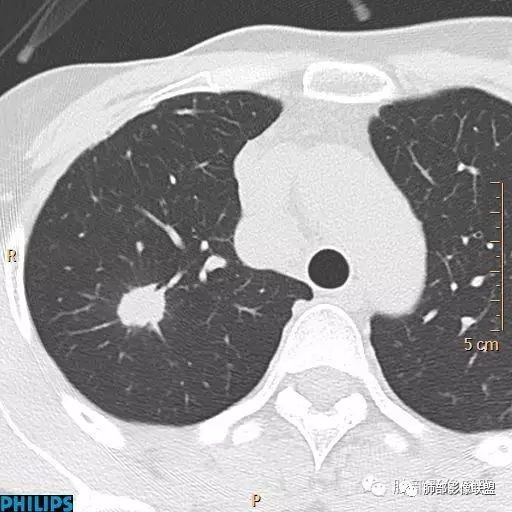

△外后基底段支气管应该堵了,深分叶,

△坏死边界不清,支持恶性。

就肺部病灶本身而言,深分叶,近端支气管显示欠佳,双侧对比还是符合堵塞,强化也支持恶性特点,那就是良性肿瘤不支持,如果要考虑良性,就是特异性感染了。

结直肠癌肺转移瘤多数边缘光整清楚,可以分叶、毛刺、空洞及强化不均匀,有时候与原发肿瘤不易鉴别;结直肠癌肺转移瘤有片状低密度区考虑与结、直肠癌含有粘液及转移性腺癌有更多的坏死成份有关。另结直肠癌中粘液腺癌远处转移灶内部可出现钙化,其病理类型属于黏液样钙化。

1.血道转移,落脚于血管末梢的肺间质,常两肺多发,随机分布,较少造成支气管阻塞,也很少见支气管穿行,罕见出现肺不张或阻塞性肺炎。

2.膨胀性生长,病灶往往较圆隆,如类圆形,边缘截然孤悬,似与相邻肺组织了无瓜葛!

3.结节影缺乏张力,或者收缩乏力,鲜有观察到毛刺。在孤立病灶,这都是与肺腺癌明显不同的。